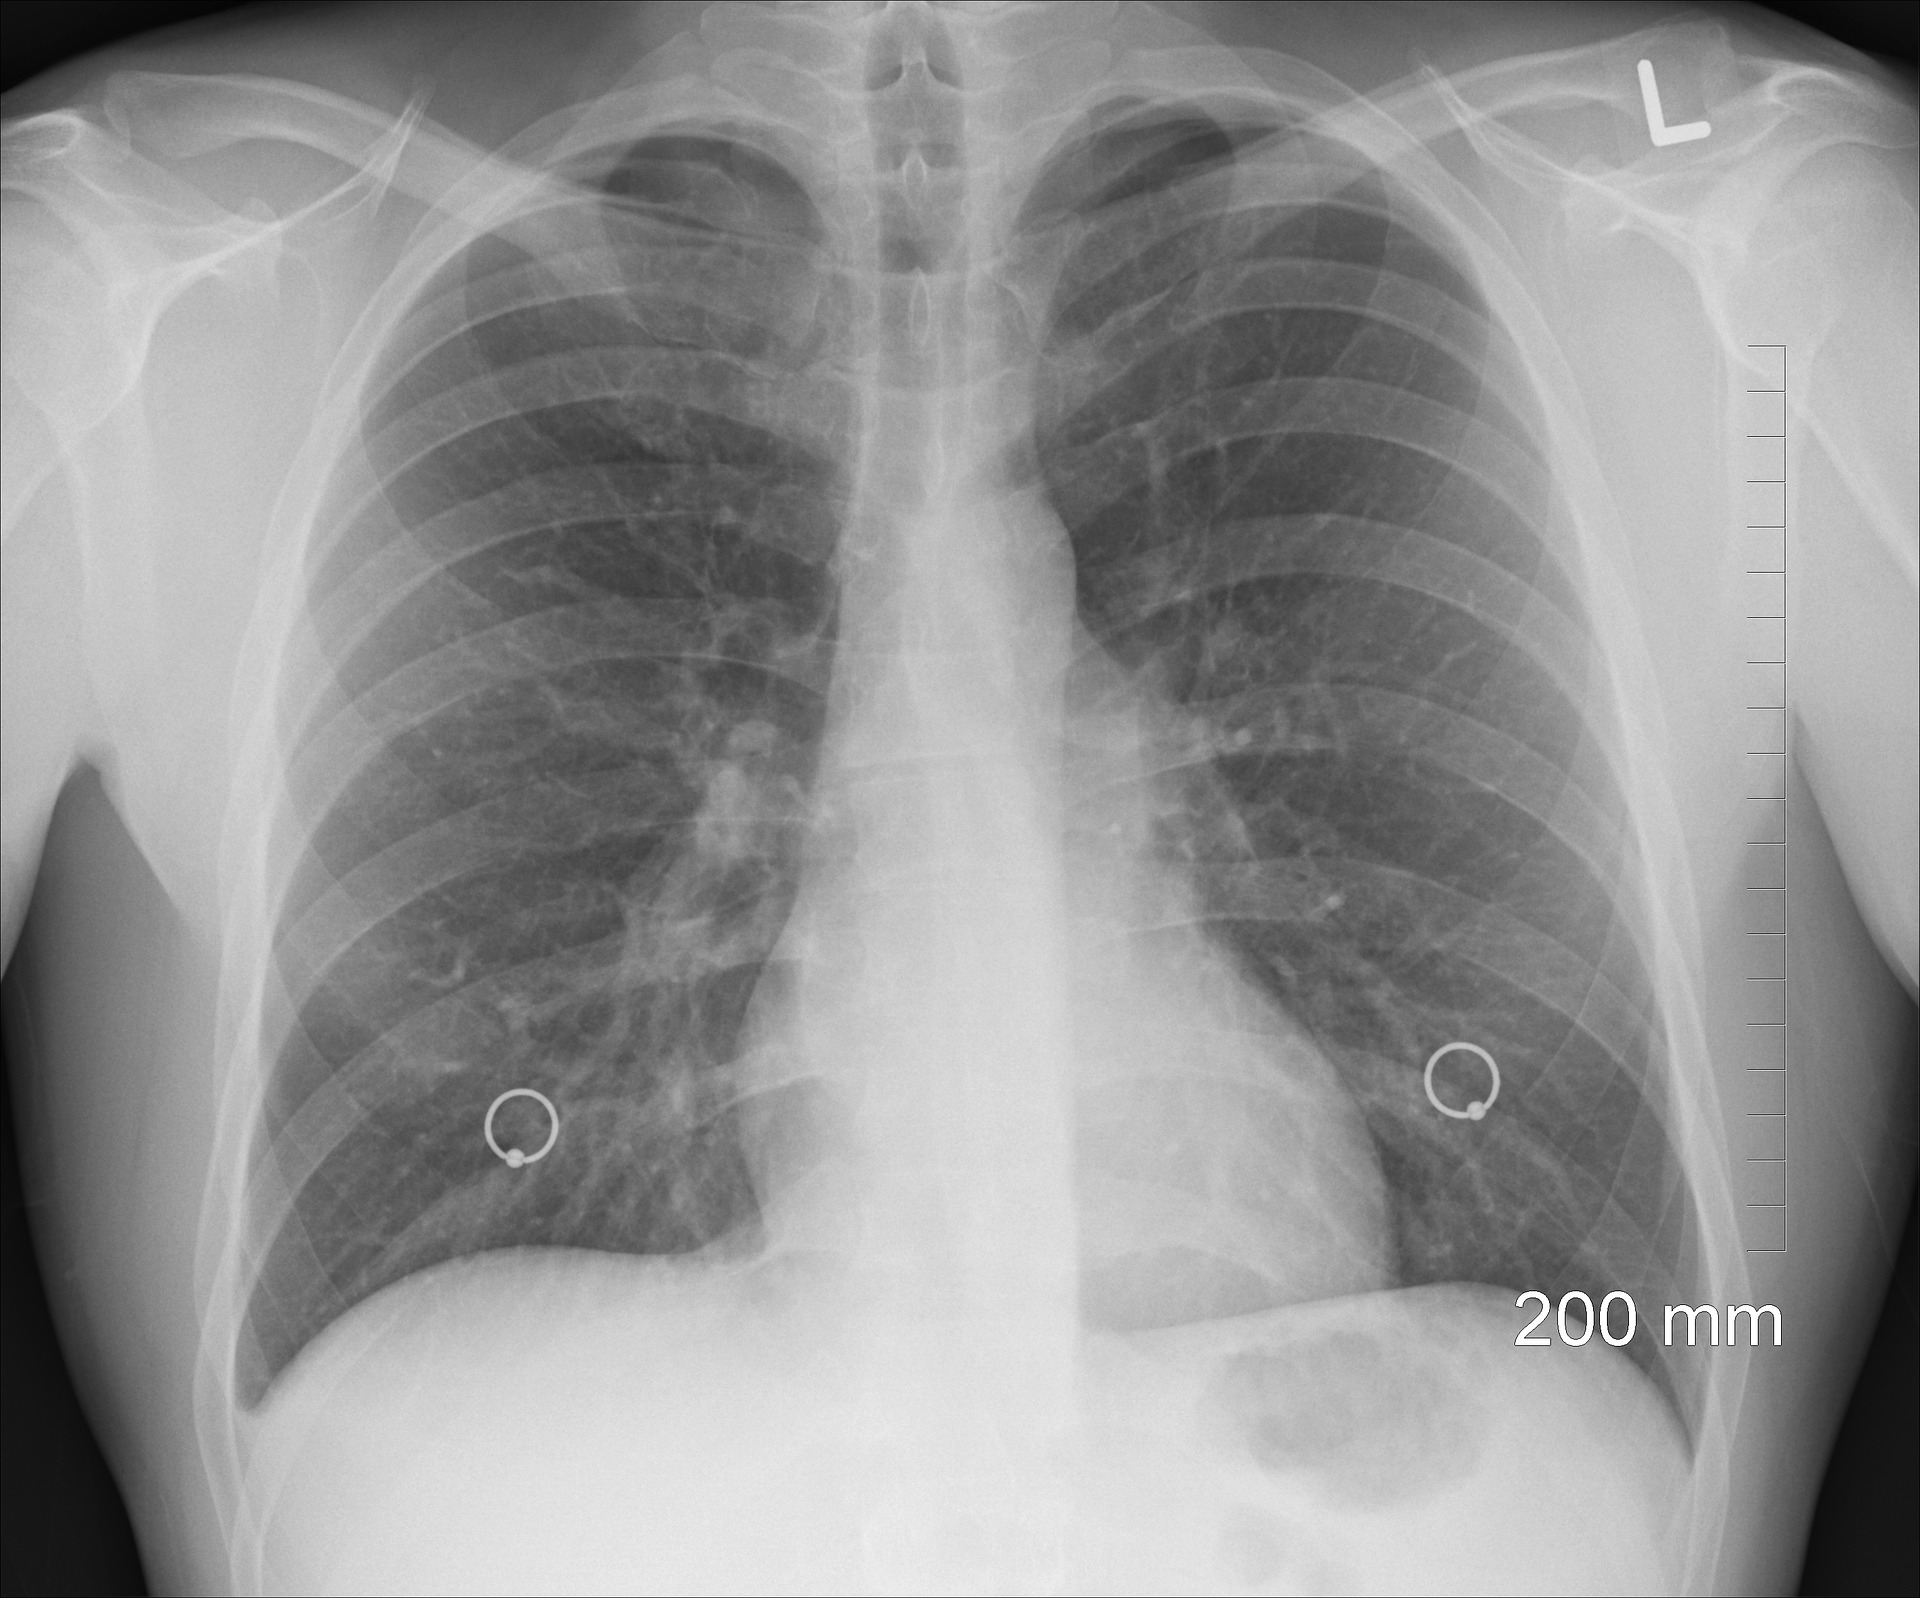

Mimo ogromnego postępu w medycynie rak płuca wciąż pozostaje jednym z największych wyzwań współczesnej onkologii. To złożona i niejednorodna choroba, która wymaga zarówno indywidualnego podejścia diagnostycznego, jak i personalizacji leczenia.

W leczeniu onkologicznym coraz większą wagę przykłada się do indywidualnego podejścia do pacjenta. Wybór terapii zależy nie tylko od rodzaju i lokalizacji nowotworu, ale także od ogólnego stanu zdrowia chorego, jego kondycji oraz chorób współistniejących. To szczególnie istotne w przypadku raka płuca. Osłabiona sprawność fizyczna części pacjentów sprawia, że nie mogą oni otrzymać standardowego leczenia, czyli chemioterapii opartej na pochodnych platyny.

Pacjenci z zaawansowanym niedrobnokomórkowym rakiem płuca, którzy ze względu na zły stan ogólny nie mogą otrzymać dwulekowej chemioterapii opartej na pochodnych platyny, stanowią grupę wymagającą szczególnego podejścia. Dla takich chorych przez długi czas jedyną opcją była chemioterapia jednolekowa – mniej obciążająca, ale też mniej skuteczna. Obecnie pojawiły się jednak nowe możliwości, w tym immunoterapia, która działa w odmienny sposób niż chemioterapia, wspierając układ odpornościowy pacjenta w walce z chorobą.